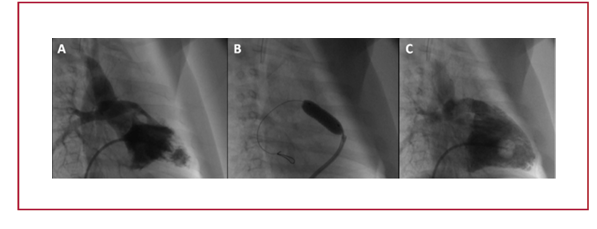

Material y métodos: Estudio multicéntrico, retrospectivo, observacional. Se incluyeron pacientes consecutivos (neonatos y lactantes menores) con diagnóstico de TOF asistidos en cuatro centros diferentes de la ciudad de Córdoba, Argentina, que recibieron stent en tracto de salida de ventrículo derecho (TSVD) como abordaje inicial de su cardiopatía congénita. La indicación de intervención paliativa inicial fue consensuada en reunión del equipo cardiovascular en cada centro participante. Una anatomía compleja (ramas pulmonares con Z score ≤ -2,5), presentación en shock cardiogénico o en crisis de cianosis, bajo peso o comorbilidades significativas (enterocolitis necrotizante, prematurez, insuficiencia renal, convulsiones) inclinaron la decisión hacia un abordaje percutáneo inicial.

Resultados: Entre agosto de 2017 hasta mayo de 2018, 6 pacientes con TOF sintomáticos recibieron stent en TSVD. La edad media fue 39,3 días (9-87), el peso medio fue 3,60 kg (2,2-5,4) y el 66% eran de sexo femenino. Los stents utilizados fueron coronarios o periféricos con un diámetro que varió entre 4,0 y 6,0 mm. La saturación periférica previa a la colocación del stent fue de 66,4% (42-77) incrementado a 90,6% (86-96) previo al alta (p < 0,001). No se registraron complicaciones durante

la intervención. El tiempo de internación fue de 7 días (1-13) y el tiempo de seguimiento fue de 106,8 días (4-292). No hubo mortalidad a los 30 días.

Conclusión: El implante de stent en TSVD en pacientes con TOF y anatomía desfavorable es una opción razonable en neonatos y lactantes menores como alternativa a la realización de una anastomosis de Blalock-Taussig modificada o corrección primaria inicial.